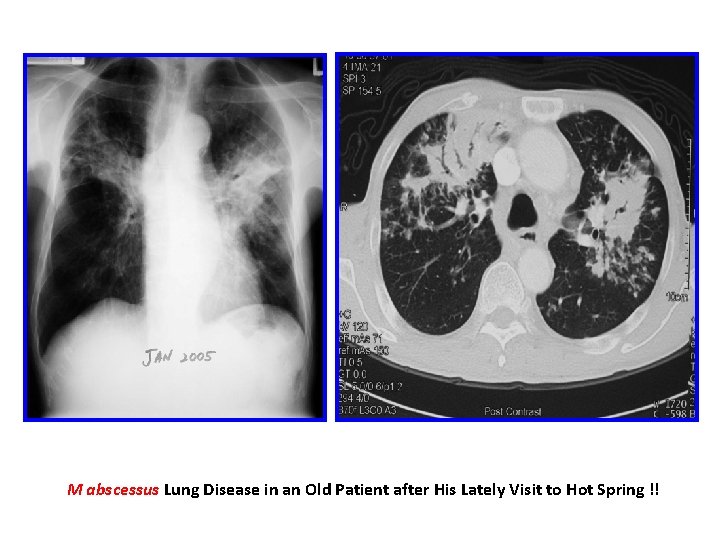

M abscessus Lung Disease in an Old Patient after His Lately Visit to Hot Spring !!